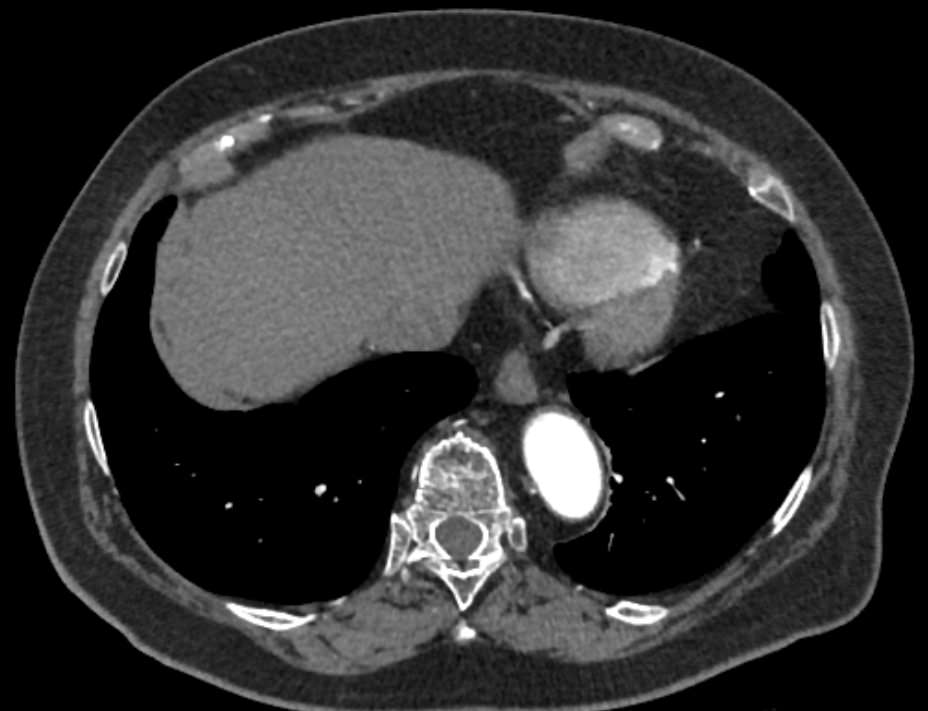

Грудная аорта делится на несколько отделов – восходящий отдел аорты, дуга аорты и нисходящий отдел. Корень аорты отходит непосредственно от левого желудочка, в его состав входят синусы Вальсальвы от которых берут начало коронарные артерии. После корня, прослеживается тубулярная часть восходящего отдела аорты, которая переходит в дугу аорты.

Дуга аорты дает начало брахиоцефальным артериям, которые питают головной мозг и верхние конечности. Затем следует нисходящий отдел аорты, распространяющийся через отверстие в диафрагме. От грудного отдела аорты отходят висцеральные артерии, кровоснабжающие органы средостения: бронхиальные, пищеводные, перикардиальные, медиастинальные артерии.

Одним из информативных методов диагностики сосудистой патологии является мультиспиральная компьютерная томография грудной аорты и ее ветвей (КТ-ангиография). Метод сканирования при помощи рентгеновских лучей и цифровой обработки данных позволяет получать послойные снимки сосудов и трехмерные реконструкции сосудистой системы в мельчайших подробностях.

Для того, чтобы качественно визуализировать сосудистую систему КТ-ангиография предусматривает в обязательном порядке применение контрастного усиления. Йодсодержащее контрастное вещество вводится пациенту внутривенно и, благодаря способности контраста поглощать рентгеновские лучи, ярко контрастирует сосудистую систему на фоне окружающих тканей.

КТ-ангиография позволяет диагностировать аневризмы аорты, сосудистые аномалии развития, воспалительные изменения стенок сосудов, пристеночные тромбы, сужения просвета сосудов за счет сдавления извне близлежащими опухолевыми образованиями.